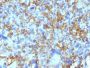

This MAb reacts with a 28 kDa chain of HLA-DRB1 antigen, a member of MHC class II molecules. It does not cross react with HLA-DP and HLA-DQ. The L243 antibody recognizes a different epitope than the LN3 monoclonal antibody, and these antibodies do not cross-block binding to each other's respective epitopes. HLA-DR is a heterodimeric cell surface glycoprotein comprised of a 36 kDa alpha (heavy) chain and a 28 kDa beta (light) chain. It is expressed on B-cells, activated T-cells, monocytes/macrophages, dendritic cells and other non-professional APCs. In conjunction with the CD3/TCR complex and CD4 molecules, HLA-DR is critical for efficient peptide presentation to CD4 T cells. It is an excellent histiocytic marker in paraffin sections producing intense staining. True histiocytic neoplasms are similarly positive. HLA-DR antigens also occur on a variety of epithelial cells and their corresponding neoplastic counterparts. Loss of HLA-DR expression is related to tumor microenvironment and predicts adverse outcome in diffuse large B-cell lymphoma.Primary antibodies are available purified, or with a selection of fluorescent CF® Dyes and other labels. CF® Dyes offer exceptional brightness and photostability. Note: Conjugates of blue fluorescent dyes like CF®405S and CF®405M are not recommended for detecting low abundance targets, because blue dyes have lower fluorescence and can give higher non-specific background than other dye colors.

Ramos, Daudi or HuT78 cells. Tonsil or lymph node

Higher concentration may be required for direct detection using primary antibody conjugates than for indirect detection with secondary antibody|Immunofluorescence: 0.5-1 ug/mL|Immunohistology formalin-fixed 0.25-0.5 ug/mL|Staining of formalin-fixed tissues is enhanced by boiling tissue sections in 10 mM citrate buffer, pH 6.0, for 10-20 min followed by cooling at RT for 20 minutes|Flow Cytometry 0.5-1 ug/million cells/0.1 mL|Western blotting 0.5-1 ug/mL|Does not react with mouse; others not known|Optimal dilution for a specific application should be determined by user